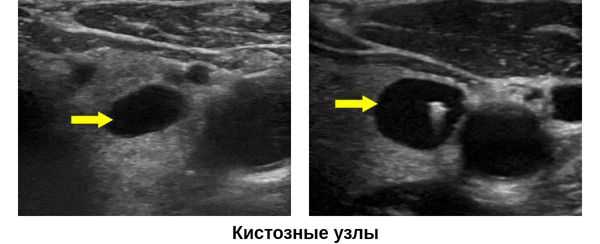

- Если коллоидная киста возникает из гиперпластического узла, то она имеет сплошной фон. Кистозные пространства переменных размеров. Солидный, четко выраженный, овальный, изоэхогенный узел, в котором нет точечной кальцификации. Коллоидные агрегаты видны разбросанными в кистозных пространствах

Ультрасонографические данные. Ультразвуковое сканирование в оттенках серого. Однокамерная тонкостенная киста является типичной находкой. У нее имеется тонкая, эхогенная стенка и анэхогенное содержимое с задним акустическим усилением. Характерны эхогенные очаги с артефактами хвоста кометы, представляющие собой взвешенные коллоидные агрегаты. ± коллоидные скопления (нерегулярный, эхогенный, аваскулярный детрит). Если было предыдущее кровоизлияние в кисту, то она будет толстостенной с детритом ± уровень жидкости. Толстые септы ± кометный хвост, если киста возникает из гиперпластического узла. Фон узла сплошной, а кистозные пространства переменных размеров. Узел будет выглядеть солидным, с хорошо выраженными границами, овальным и, изоэхогенным, а внутри не обнаруживается точечной кальцификации. Коллоидные скопления разбросаны в кистозных пространствах